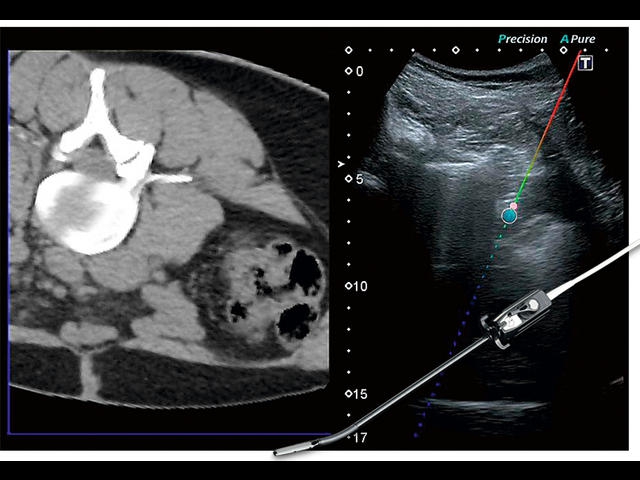

Обновленная версия легендарного УЗ-сканера. Стационарный аппарат экспертного класса Aplio 500 Toshiba NEW, визуализирует анатомические структуры в высоком разрешении. Модель позволяет выявить микрокальцификаты, новообразования, нарушения в работе сердца, сосудов и мышц. Присутствует функция виртуальной эндоскопии, 4D-сканирования, эластометрии тканей, УЗИ с контрастированием. За повышение качества изображения отвечают технологии ApliPure и Superb Microvascular Imaging. Первая задействует возможности пространственного и частотного кодирования, формирует цельный визуальный ряд с сохранением клинических маркеров. Вторая улучшает отображение микрососудистого русла, используя доплеровский эффект. Модель оснащена 21-дюймовым монитором, имеет 4 активных порта. Возможно подключение педиатрических, интраоперационных, лапароскопических и чреспищеводных датчиков.

• Fly Thru. Виртуальная эндосонография обеспечивает построение трехмерной модели полостей, протоков и сосудов в рельном времени, облегчает организацию инвазивных процедур и динамических исследований. Посредством Fly Thru можно установить шунты и стенты, проводить точные оперативные вмешательства.